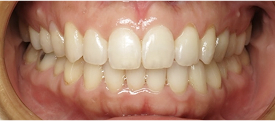

Patient treated with braces

Before

After